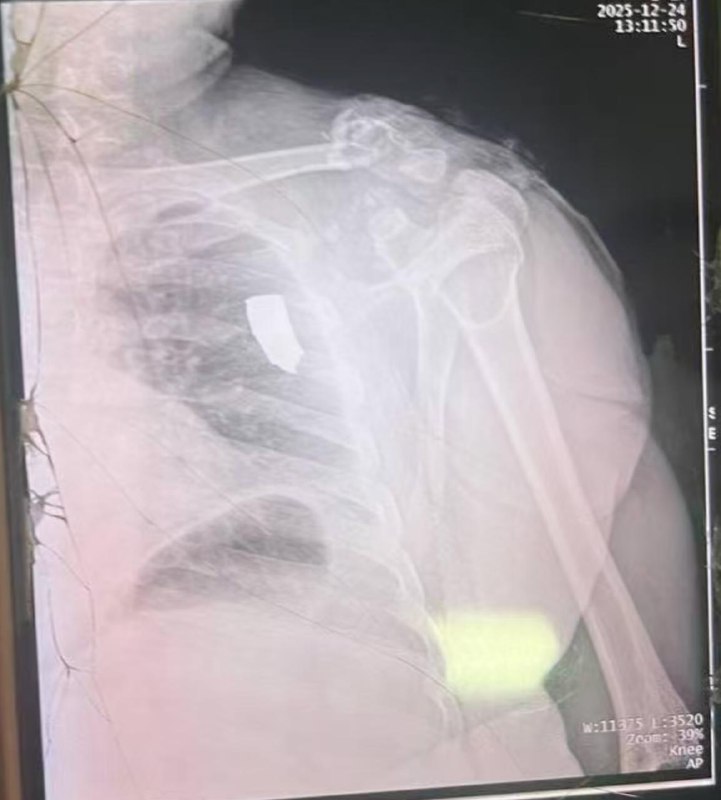

#网友投稿:昨天我兄弟让泰军给炸了!

坐标波贝,昨天就在我们房子旁不远,柬军开着三辆坦克,躲在物业后面向泰军打炮,把我们中国人当肉盾。

泰军也毫不客气的反击,一发炮弹过来,就在我们不远处爆炸,一块弹片飞来,击中了我的好兄弟,现在躺在医院里面,生死未卜!